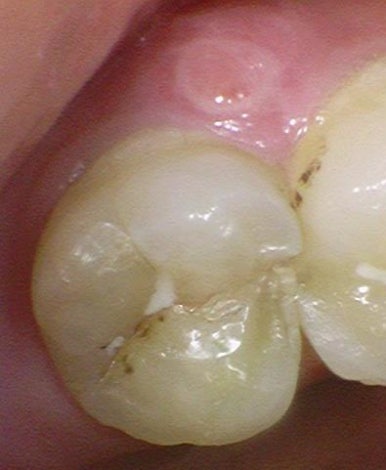

실제 케이스 2

간혹 치아 금이 가서 약간씩 통증이 있을 때

빨리 씌우지 않고 방치하면 더 쪼개져서 발치로 가는 경우가 매우 흔합니다.

쪼개져서 금이 보이고, 염증이 생겨서 부은 치아(동일치아)